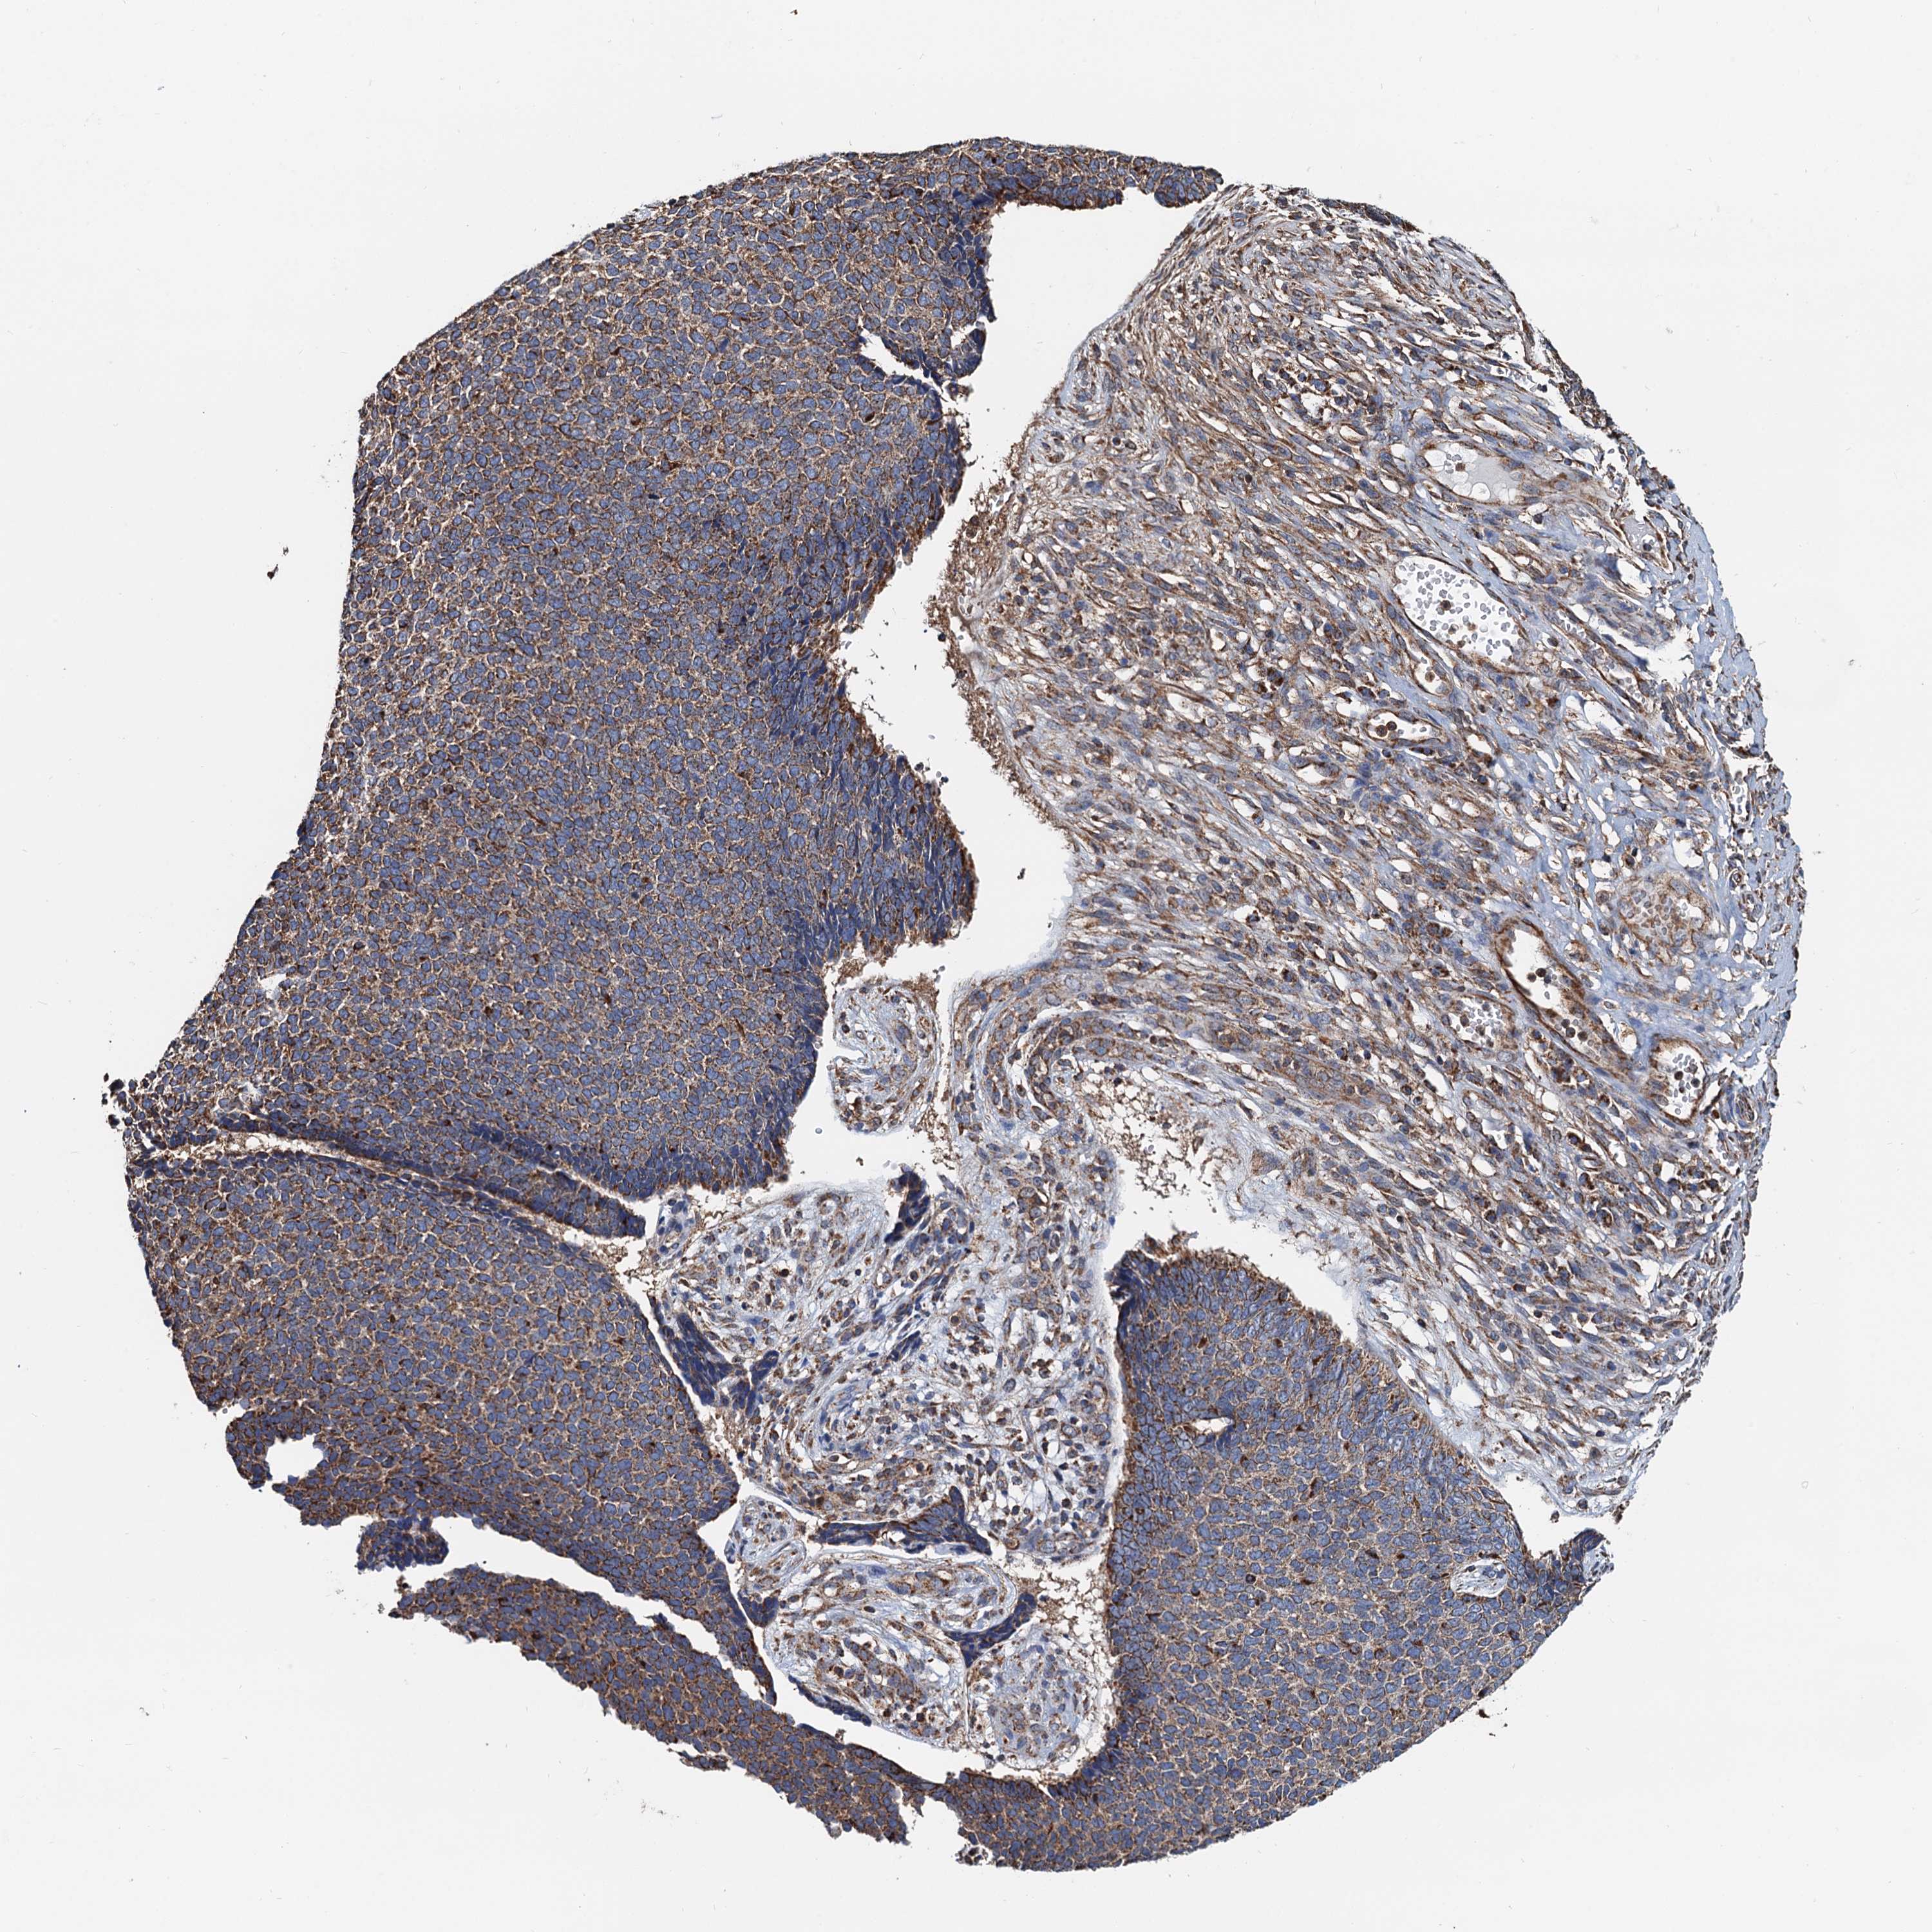

Basal cell and squamous cell cancer

SKIN CANCER - Protein expressioni

A mouse-over function shows sample information and annotation data. Click on an image to view it in a full screen mode. Samples can be filtered based on level of antibody staining by selecting one or several of the following categories: high, medium, low and not detected. The assay and annotation is described here.

Antibody stainingi

Antibody staining in the annotated cell types in the current human tissue is reported as not detected, low, medium, or high, based on conventional immunohistochemistry profiling in selected tissues. This score is based on the combination of the staining intensity and fraction of stained cells.

Each image is clickable and will lead to virtual microscopy that enables deeper exploration of all samples and also displays staining intensity scores, fraction scores and subcellular localization as well as patient and tissue information for each sample.

Antibody HPA039371

Antibody HPA040174

Staining

High

Medium

Low

Not detected

Intensity

Strong

Moderate

Weak

Negative

Quantity

>75%

75%-25%

<25%

None

Location

Nuclear

Cytoplasmic/membranous

Cytoplasmic/membranous,nuclear

Basal cell carcinoma

Squamous cell carcinoma, NOS

Squamous cell carcinoma, metastatic, NOS